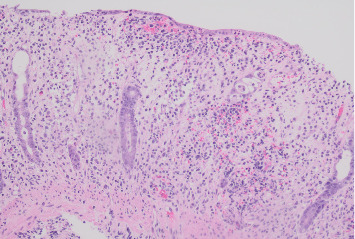

Diagnosing inflammatory bowel disease (IBD) can be challenging in the presence of mimicking conditions, such as infectious colitis. An accurate diagnosis is important to avoid unnecessary treatment. Nontyphoidal Salmonella species are an important cause of infectious colitis that at times can mimic IBD. Salmonella enterica serotype Saintpaul has caused numerous fatal foodborne gastroenteritis outbreaks worldwide. It has also been known to cause other infections, such as bacteremia, splenic abscesses, and meningitis, but has only rarely been known to cause colitis. Worryingly, antibiotic resistance rates of S. Saintpaul are rising. This case report presents a woman with S. Saintpaul colitis mimicking Crohn's disease. Despite an initial plan to start biologic therapy, long-term follow-up while off immunosuppressant therapy confirmed S. Saintpaul as the underlying cause of colitis, sparing our patient long-term immunosuppression. This case highlights the importance of ruling out infectious colitis before beginning long-term immunosuppressive therapy and the challenges of mimicking conditions as well as the novelty of the Saintpaul serotype causing colitis.

Abstract Image